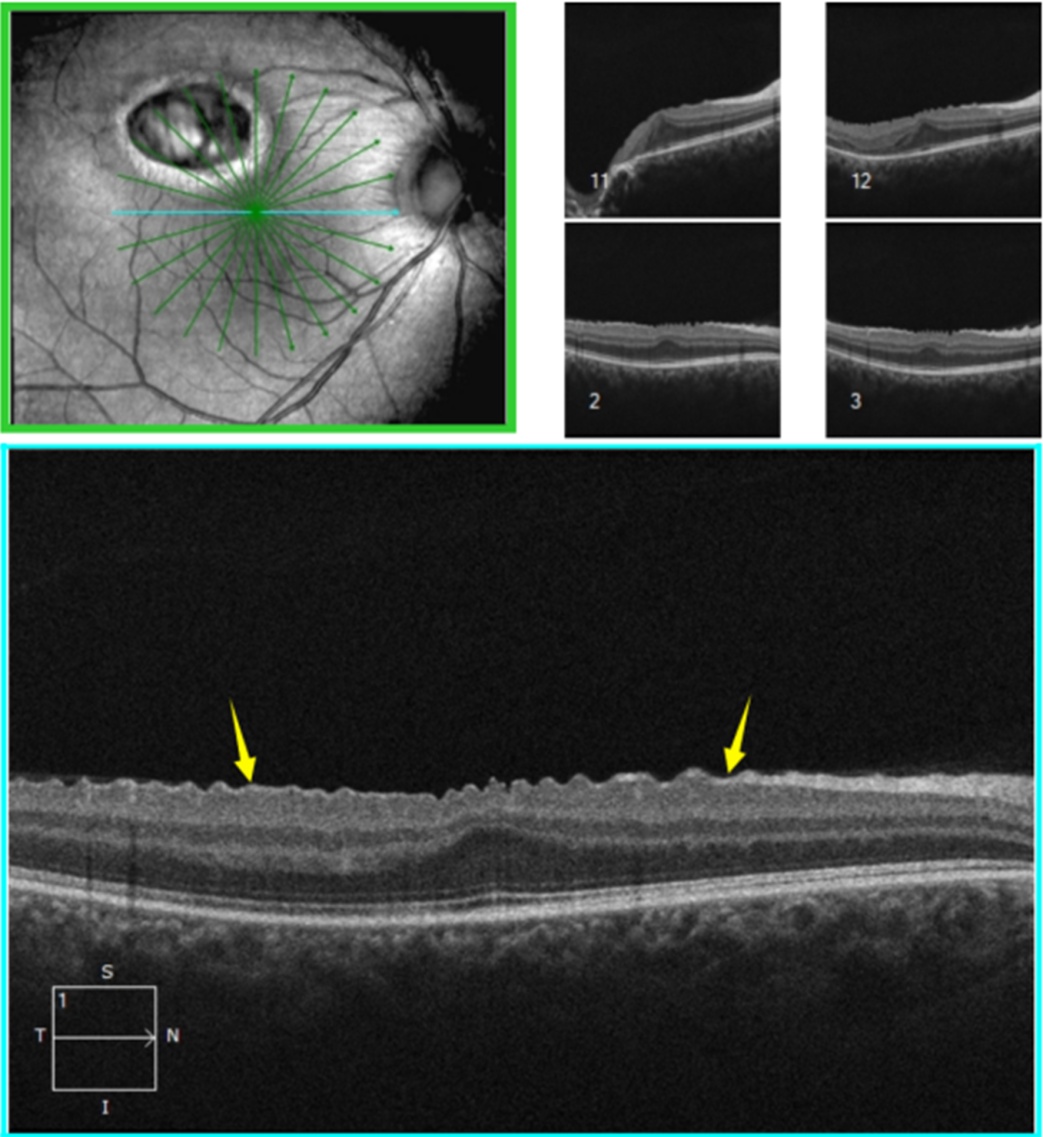

黄斑相关光层析成像术示:右眼黄斑区附近内界膜呈齿状凸起,黄斑中心凹处外丛状层呈局限性隆起(见图2);病灶区视网膜脉络膜组织随巩膜组织向外凹陷,凹陷区域内视网膜神经上皮层变薄及缺损,神经上皮层间可见部分缺损及浅脱离(见图3)。左眼OCT未见明显异常。

Figure 2. The yellow arrow indicates a dentate protrusion of the internal limiting membrane near the macular area of the right eye

2. 黄色箭头所指示右眼黄斑区附近内界膜呈齿状凸起

Figure 3. The blue arrow indicates the absence of retinal and choroidal tissue in the lesion area, with thinning and defects in the retinal pigment epithelium (RPE) layer within the depressed region

3. 蓝色箭头所指示病灶区视网膜、脉络膜组织缺失,凹陷区域内RPE层变薄及缺损